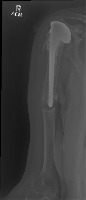

trish abnormal/normal Computer Vision Project

Medical Diagnostics: The model can be used in hospitals, clinics, or doctor practices to help provide a quick preliminary diagnosis for patients, especially in urgent care settings. Identifying fractures and hairline fractures can expedite treatment and intervention plans.

Telemedicine App: The model can be integrated into telemedicine applications to provide virtual first-line diagnostics for patients who cannot readily access medical facilities. This is particularly useful in remote areas and for elderly or disabled people.

Emergency Rescue: The model can be used by rescue teams in disaster-stricken areas to quickly identify serious injuries that need immediate attention, allowing for more informed decision-making and prioritization of patients.

Training Medical Students: This model can be used to educate medical students in the process of identifying fractures and hairline fractures, providing valuable, hands-on training experience without the risks associated with real-world diagnostics.